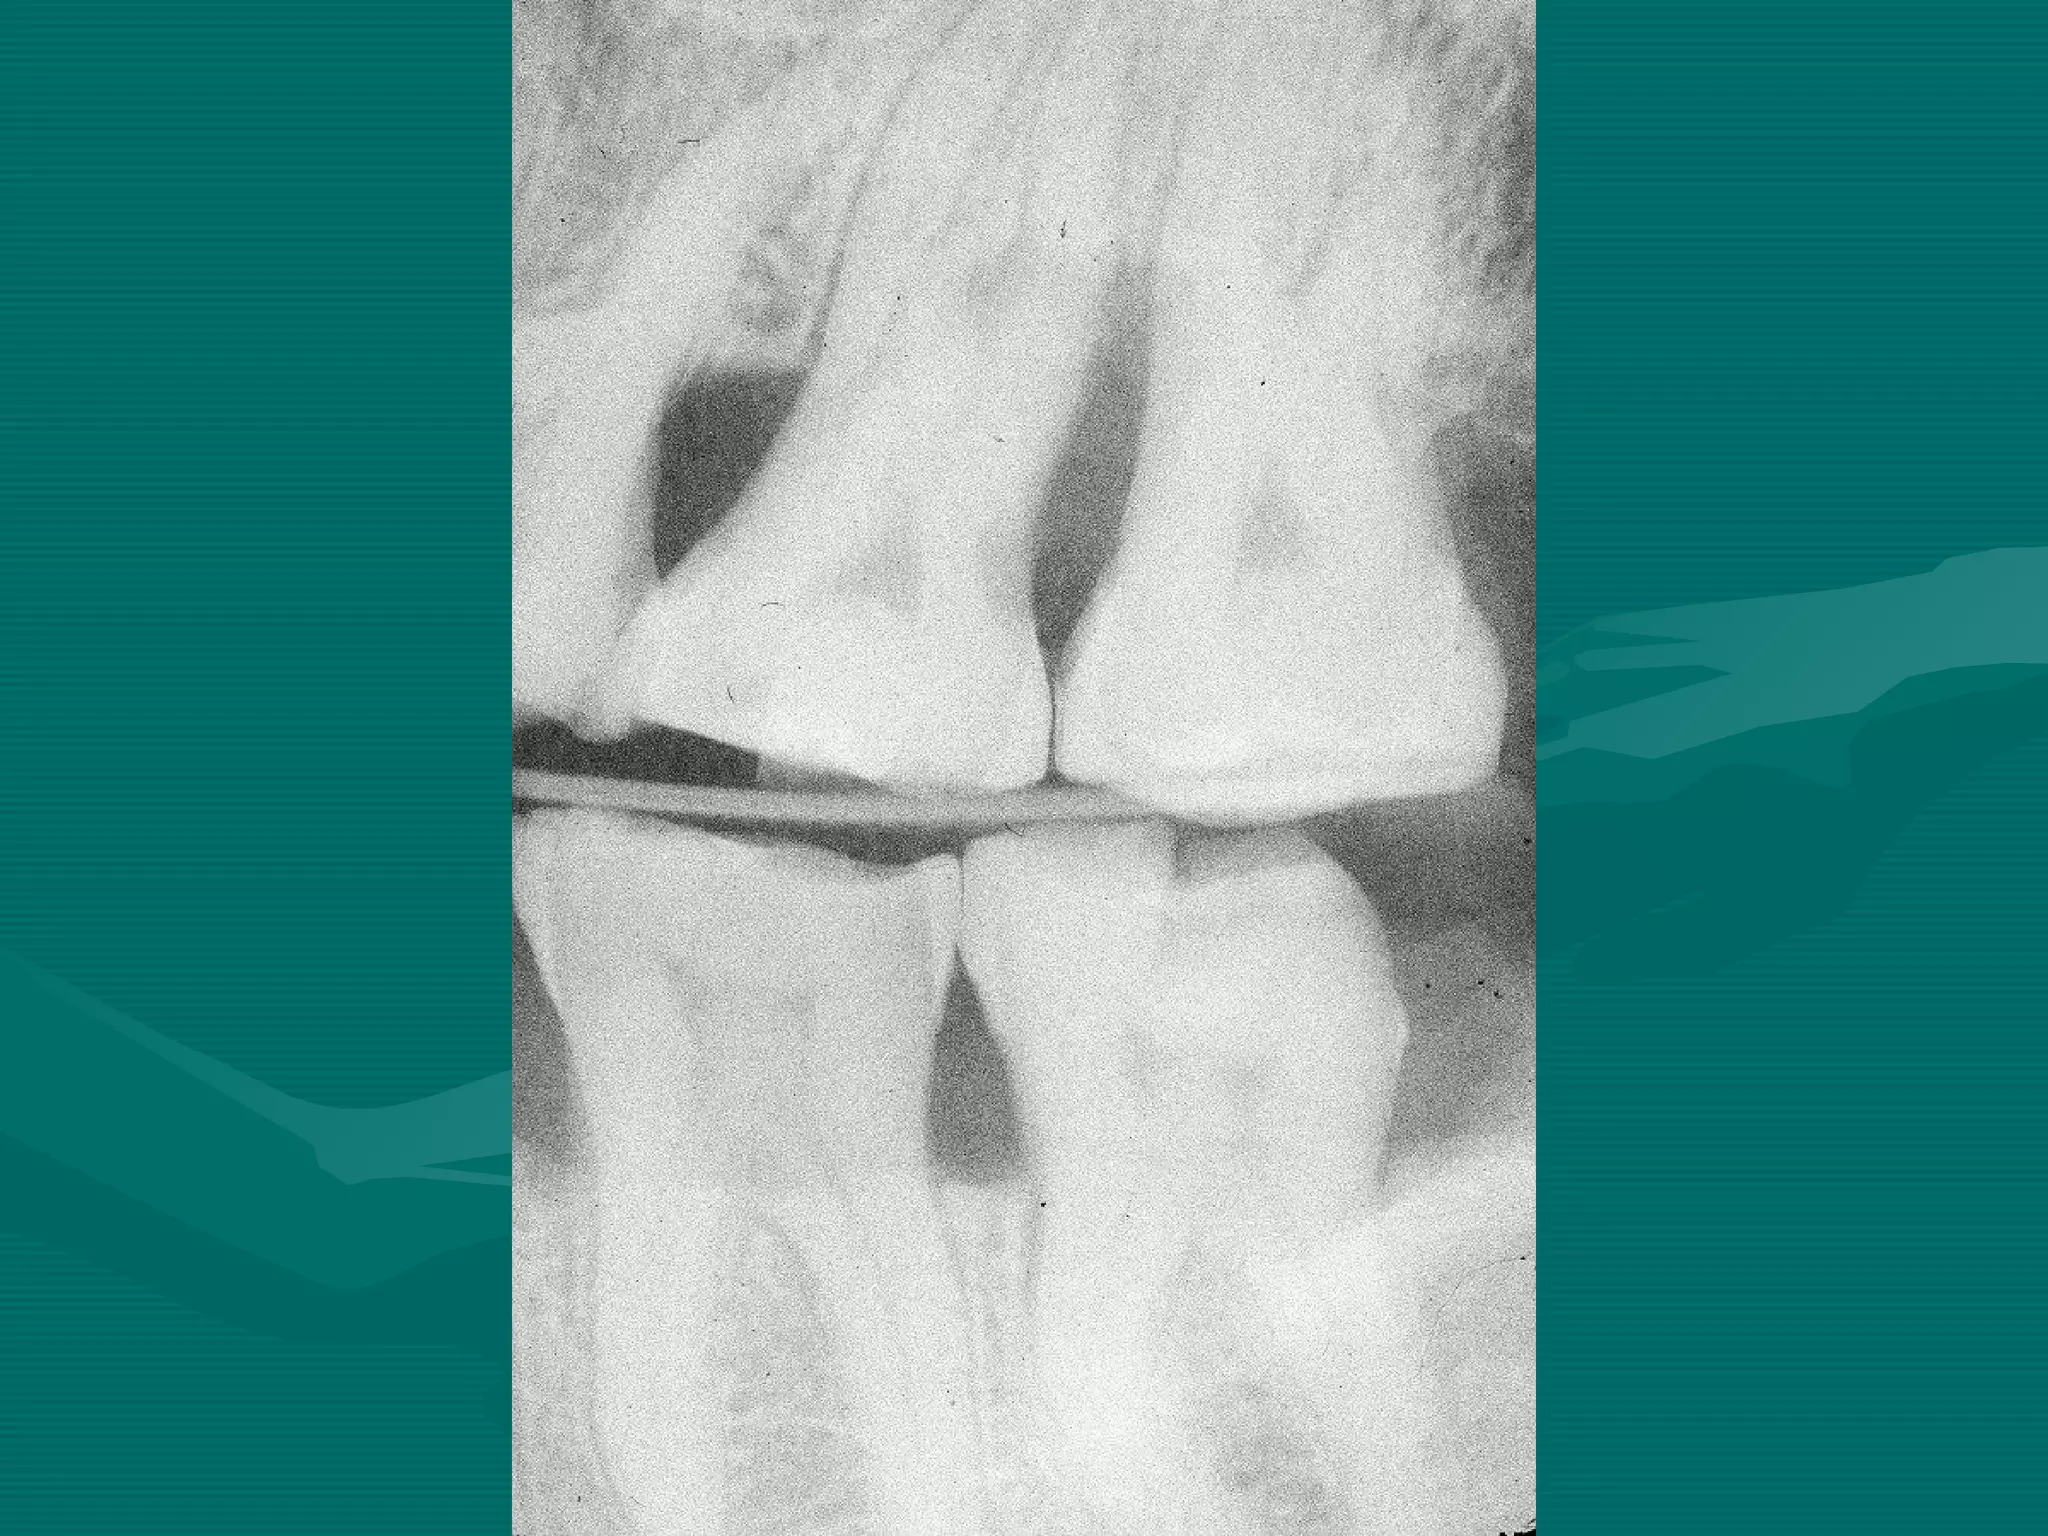

BITEWING

ERRORS

Bite-wing Technique ErrorsBite-wing Technique Errors

Patient is not biting on the bite block

Film placement

Film bending

Horizontal angulation

Single overlap. Technique OK

Cone cut

Film Reverse